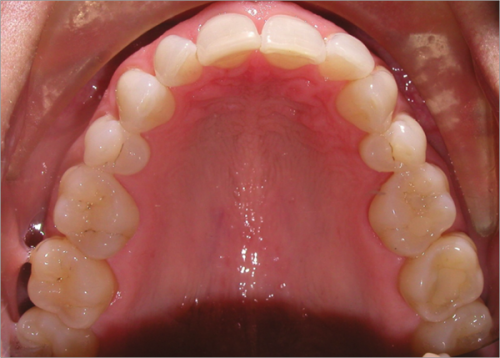

44 year old female:

Diagnosis:

- Upper and lower arch collapse due to missing teeth

- Retrusive angulation of upper & lower front teeth

- Severe collision and wear of front teeth

Treatment:

- Combination of Invisalign and braces

- Creating space for placement of an implant in the lower arch

- 28 months